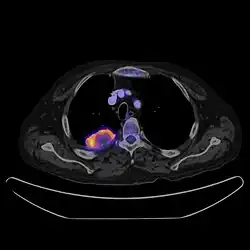

PET/CT je diagnostická zobrazovací metoda spojující vyšetření počítačovou tomografií (CT) a pozitron emisní tomografií (PET). Získané obrazy obsahují jak poměrně podrobnou informaci o anatomické stavbě, tak i informaci o metabolické aktivitě tkání.